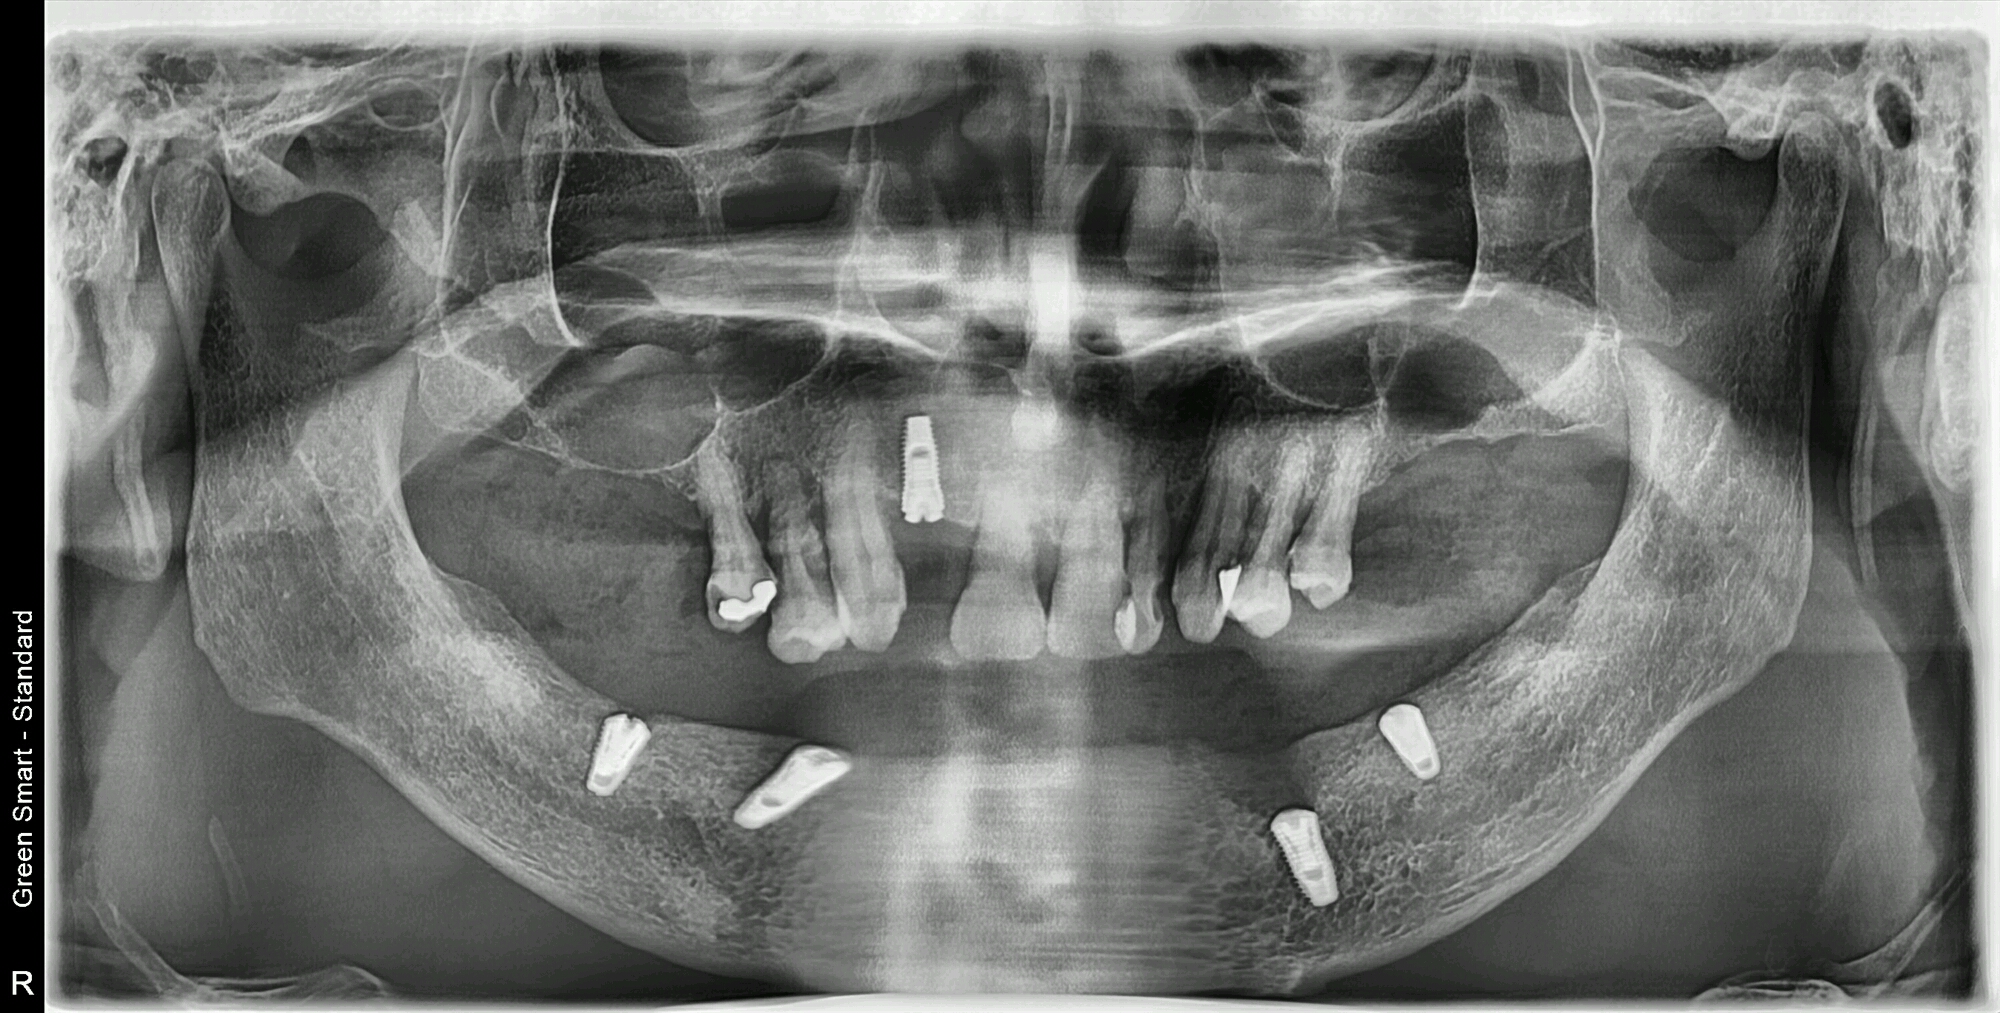

維港歡樂牙科謝醫生介紹:可以選擇all-on-4 植牙修復,同時,謝醫生分享咗一例All on 4的植牙個案。湯先生下排牙齒缺失,進行all on 4 一期植牙,上排種植一顆,當天完成一期手術植體植入,待三個月後進行二期植牙修復。

採用植體:南韓登騰種植體

植牙方式:All-on-4